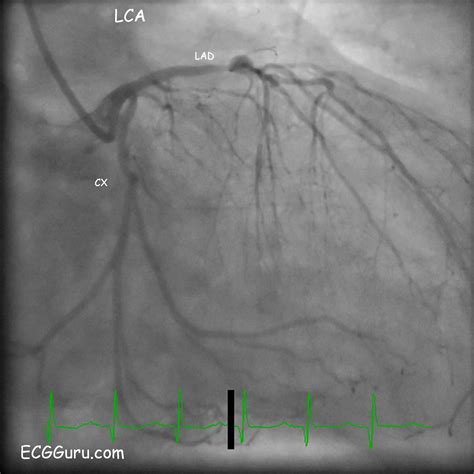

Cardiac Catheterization The gold standard for directly visualizing the artery via angiography.

The Left Circumflex Artery originates from the left main coronary artery, which bifurcates shortly after leaving the aorta. While the left anterior descending (LAD) artery travels down the front of the heart, the LCx takes a different path, winding around the left side of the heart within the atrioventricular groove. This strategic positioning allows it to supply blood to critical areas that other vessels might not reach.